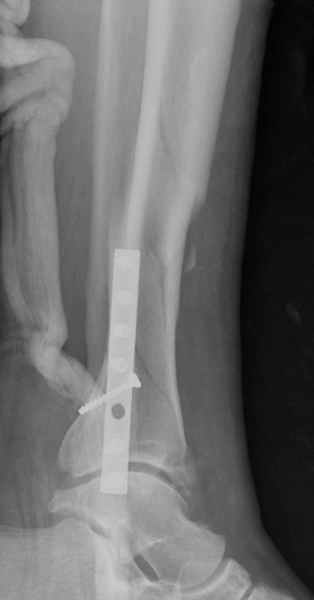

У меня молодой врач на линии, снимки отправил через эл. почту,

спрашивает что делать с больным который поступил недавно, фермер 55 лет падение при пьяной драке в баре, года два назад перенес операцию на лодыжке, на снимках и КТ перелом без вовлечения сустава,

Повреждение такой локализации, на которой применимы и аппарат (классический Илизарова или гибридный), пластина, особенно Locked Plate, и гвоздь с блокированием. В нашей клинике был бы выполнен закрытый интрамедуллярный остеосинтез. Желательно использовать гвоздь с возможностью провести более чем 2 обычных фронтальных винта в дистальном отломке.

При такий спирали задний край tibia может быть сломан - нет ли этого в данном случае? На всякий случай можно было ввести 1-2 винта 4,5 мм спереди назад мимо гвоздя. Хотя самый дистальный блокирующий винт, возможно, зацепил этот отломок. А какой тут диаметр гвоздя и locking винтов?